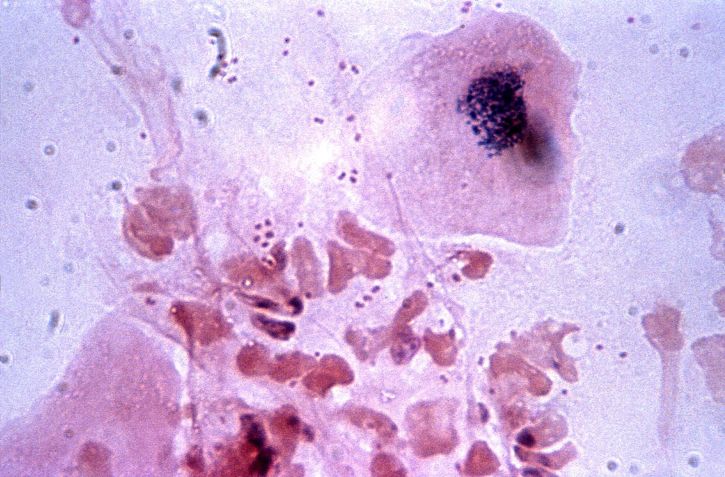

백혈구는 체내의 감염과 싸우는 중요한 세포로, 혈액 1마이크로리터당 4000~10,000개가 정상적으로 존재해야 합니다. 이들 백혈구는 호중구, 호산구, 호염기구 등으로 구성되어 있으며, 그 중 호중구의 비율이 가장 높습니다. 이들은 세균이나 바이러스와 같은 침입자의 공격에 맞서 싸우며 우리 몸을 방어하는 역할을 합니다. 백혈구가 적혈구에 비해 상대적으로 적은 수치에도 불구하고, 그 역할은 매우 중요합니다. 백혈구 수치가 감소하게 되면 체내 감염에 대한 저항력이 떨어지게 되어 다양한 건강 문제가 발생할 수 있습니다.

또한, 바이러스 감염이나 자가면역질환과 같은 전신성 염증 상태에서도 백혈구 수치가 감소할 수 있습니다. 특히, 항암 치료를 받는 환자에게서도 백혈구 수치 감소가 흔히 나타납니다. 이런 경우에는 면역력이 저하되어 감염에 취약해지므로, 감염 예방을 위한 철저한 관리가 필요합니다. 백혈구 수치가 낮아지면 신체가 세균이나 바이러스에 쉽게 감염될 수 있으므로, 주의가 요구됩니다.